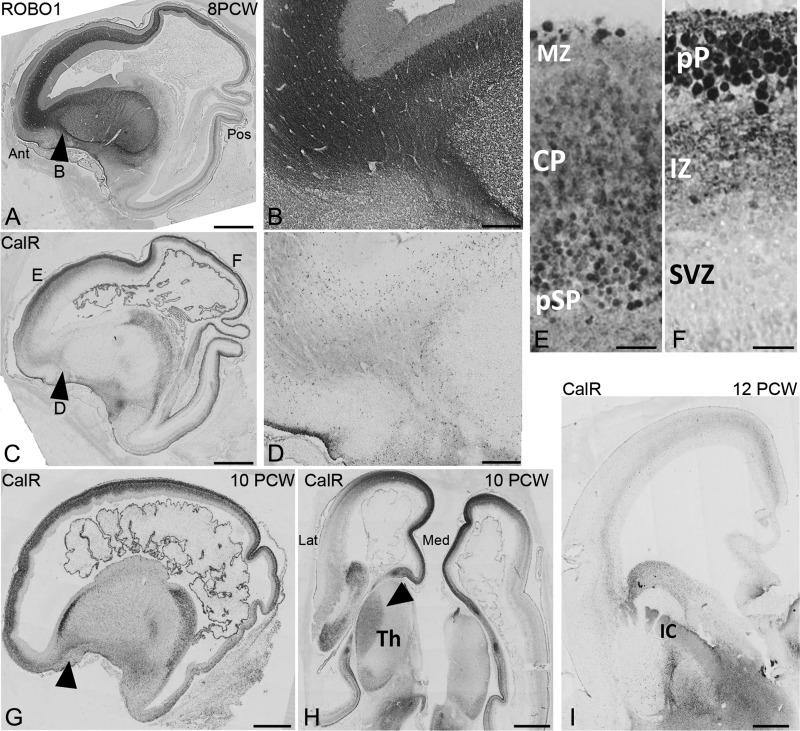

The current model, based on rodent data, proposes that thalamocortical afferents (TCA) innervate the subplate towards the end of cortical neurogenesis. This implies that the laminar identity of cortical neurons is specified by intrinsic instructions rather than information of thalamic origin. In order to determine whether this mechanism is conserved in the primates, we examined the growth of thalamocortical (TCA) and corticofugal afferents in early human and monkey fetal development. In the human, TCA, identified by secretagogin, calbindin, and ROBO1 immunoreactivity, were observed in the internal capsule of the ventral telencephalon as early as 7-7.5 PCW, crossing the pallial/subpallial boundary (PSB) by 8 PCW before the calretinin immunoreactive corticofugal fibers do. Furthermore, TCA were observed to be passing through the intermediate zone and innervating the presubplate of the dorsolateral cortex, and already by 10-12 PCW TCAs were occupying much of the cortex. Observations at equivalent stages in the marmoset confirmed that this pattern is conserved across primates. Therefore, our results demonstrate that in primates, TCAs innervate the cortical presubplate at earlier stages than previously demonstrated by acetylcholinesterase histochemistry, suggesting that pioneer thalamic afferents may contribute to early cortical circuitry that can participate in defining cortical neuron phenotypes.

目前的模型基于啮齿动物数据,提出丘脑皮质传入(TCA)在皮质神经发生末期支配基板。这意味着皮质神经元的层状身份是由内在指令决定的,而不是来自丘脑的信息。为了确定这种机制在灵长类动物中是否保守,我们检查了早期人类和猴子胎儿发育中丘脑皮质(TCA)和皮质传出传入的生长情况。在人类中,通过 secretagogin、calbindin 和 ROBO1 免疫反应性鉴定的 TCA,早在 7-7.5 PCW 时就可以在腹侧端脑的内囊中观察到,在 calretinin 免疫反应性皮质传出纤维之前通过皮层/基板边界(PSB)。此外,TCA 被观察到穿过中间区并支配背外侧皮质的基板前区,并且在 10-12 PCW 时 TCA 已经占据了大部分皮质。在狨猴中的等效阶段的观察结果证实,这种模式在灵长类动物中是保守的。因此,我们的结果表明,在灵长类动物中,TCA 比以前通过乙酰胆碱酯酶组织化学显示的更早地支配皮质基板前区,这表明先驱性丘脑传入可能有助于早期皮质回路的形成,从而参与定义皮质神经元表型。